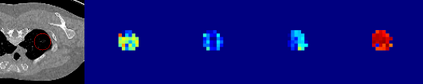

Evaluating lesion progression and treatment response via longitudinal lesion tracking plays a critical role in clinical practice. Automated approaches for this task are motivated by prohibitive labor costs and time consumption when lesion matching is done manually. Previous methods typically lack the integration of local and global information. In this work, we propose a transformer-based approach, termed Transformer Lesion Tracker (TLT). Specifically, we design a Cross Attention-based Transformer (CAT) to capture and combine both global and local information to enhance feature extraction. We also develop a Registration-based Anatomical Attention Module (RAAM) to introduce anatomical information to CAT so that it can focus on useful feature knowledge. A Sparse Selection Strategy (SSS) is presented for selecting features and reducing memory footprint in Transformer training. In addition, we use a global regression to further improve model performance. We conduct experiments on a public dataset to show the superiority of our method and find that our model performance has improved the average Euclidean center error by at least 14.3% (6mm vs. 7mm) compared with the state-of-the-art (SOTA). Code is available at https://github.com/TangWen920812/TLT.